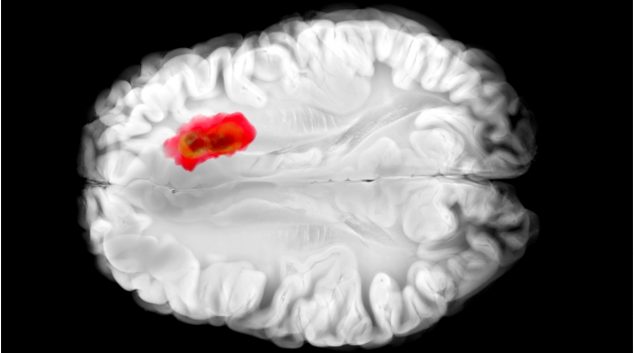

Додека водечките истражувачи во областа на вештачката интелигенција предупредуваат на лимитите на моменталната технологија, сосема поинаков пристап добива внимание: користење на живи човечки мозочни клетки како хардвер за пресметување. Овие „биокомпјутери“ се уште се во многу рана фаза – можат да играат едноставни игри како Понг и да обработуваат основно препознавање на говор. Но возбудата …